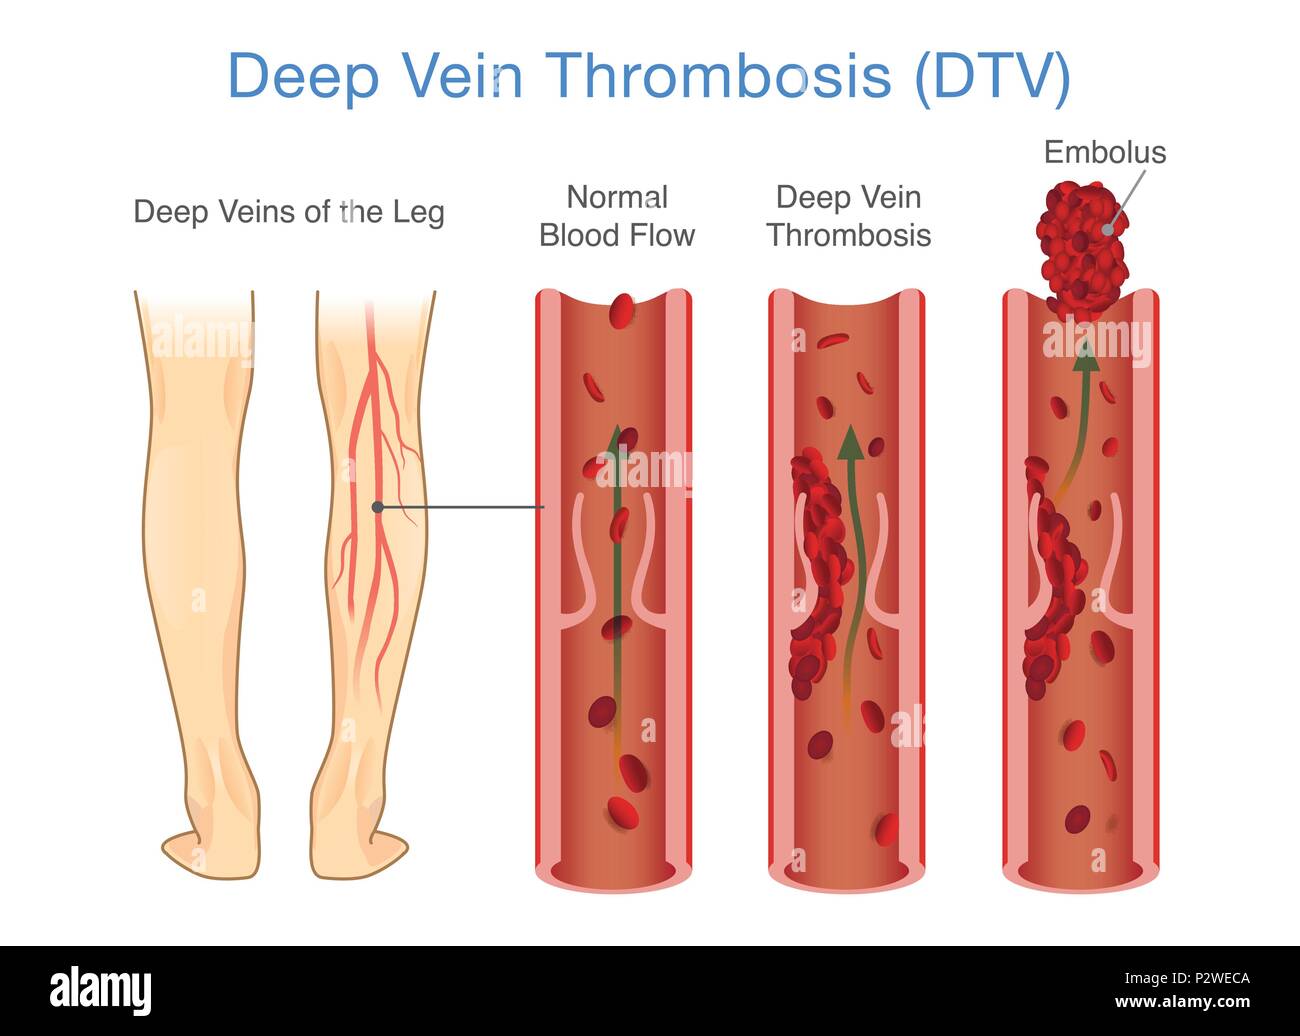

Medical Diagram of Deep Vein Thrombosis at leg area. Stock Vectorhttps://www.alamy.com/image-license-details/?v=1https://www.alamy.com/medical-diagram-of-deep-vein-thrombosis-at-leg-area-image208313850.html

Medical Diagram of Deep Vein Thrombosis at leg area. Stock Vectorhttps://www.alamy.com/image-license-details/?v=1https://www.alamy.com/medical-diagram-of-deep-vein-thrombosis-at-leg-area-image208313850.htmlRFP2WECA–Medical Diagram of Deep Vein Thrombosis at leg area.